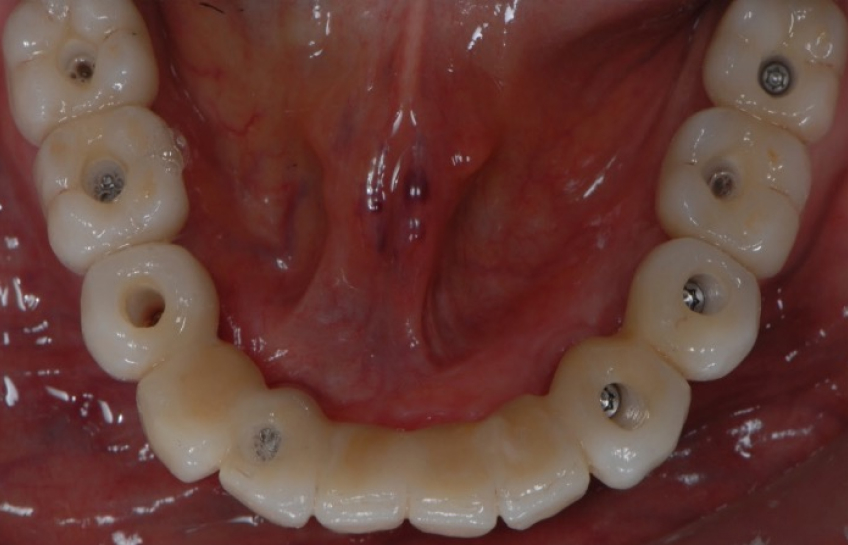

The following picture, depicts a prosthetic solution that can be described as:

- “Cad cam -generated.

- implant supported.

- screw retained.

- Segmented.

- Zirconia framework.

- Ceramic-layered reconstruction.

It becomes quite simple to fall into the curse of knowledge by solely listing the six elements of design that describe this prosthesis without providing fundamental background information on the materials and other specifications.